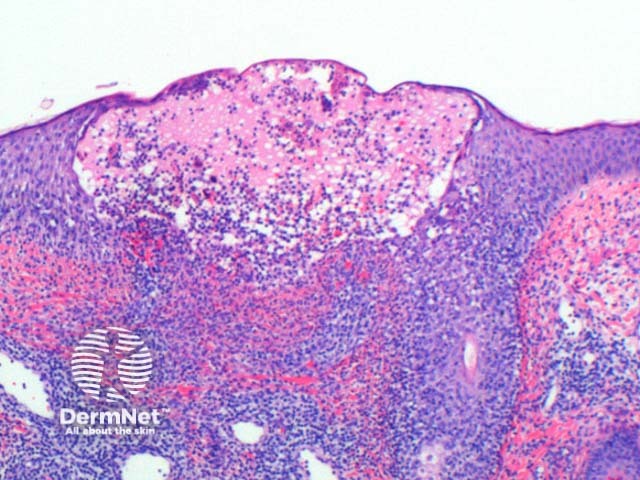

The histology of herpes infections is very distinctive. The low power pattern of a typical lesion is of an intraepidermal blister (Figure 1). The key feature is acantholysis with solitary keratinocytes within the blister cavity (Figures 1,2,3). Keratinocytes will show nuclear changes in viral infection. These included margination of the nuclear chromatin, multinucleation and nuclear inclusions (Figures 3,4,5). The viral inclusions are small pink deposits with a clear halo seen within the nucleus. When present in herpes virus infection and present with the other nuclear changes of this infection they are called Cowdry Type A inclusions. Cowdry Type B inclusions are associated with other infections such as poliovirus and do not have the other nuclear changes of herpes infection.

Figure 1